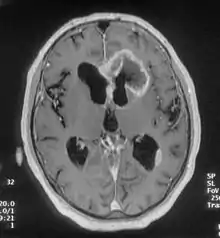

There are many different causes of frontal lobe epilepsy ranging from genetics to head trauma that result in lesions in the frontal lobes. Although frontal lobe epilepsy is often misdiagnosed, tests such as prolonged EEG monitoring, video EEG and/or an MRI scan of the frontal lobes can be administered in order to reveal the presence of a tumor or vascular malformation. Unlike most epileptic EEGs, the abnormalities in FLE EEGs precede the physical onset of the seizure and aid in localization of the seizure's origin.[4] Medications such as anti-epileptic drugs can typically control the onset of seizures, however, if medications are ineffective the patient may undergo surgery to have focal areas of the frontal lobe removed.